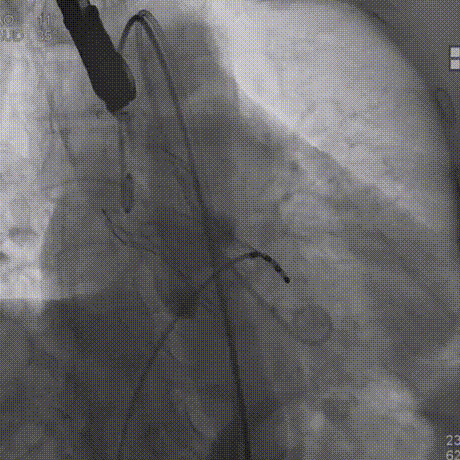

180bpm下置入23mm球囊扩张,沿导丝送入美敦力Evolut PRO经导管主动脉瓣膜系统,采用美敦力独有的commissural alignment技术,最大程度保护冠脉。递送系统顺利送入动脉系统并顺利过弓跨瓣,在最终目标位置完美释放,瓣膜立即工作。展开形态良好,无瓣周漏,无冠脉阻挡,无传导阻滞发生,术后无跨瓣压差,血液动力学稳定,手术圆满成功。

过弓跨瓣

瓣膜释放